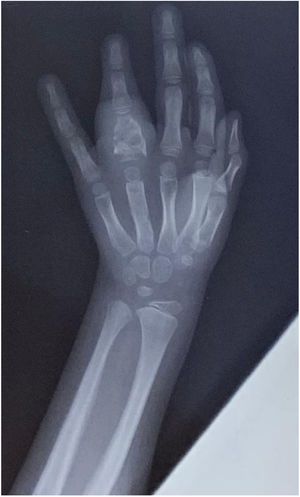

Radiography of the hands, spine, and elbows showed osteolytic lesions in the phalanx of the fourth finger of the left hand (Fig. 2) and the left elbow. Abdominal ultrasound and chest radiography showed no abnormalities. A whole-body bone scan showed increased uptake at the fourth finger of the left hand, the proximal epiphysis of the left humerus and ulna, and the right ankle.